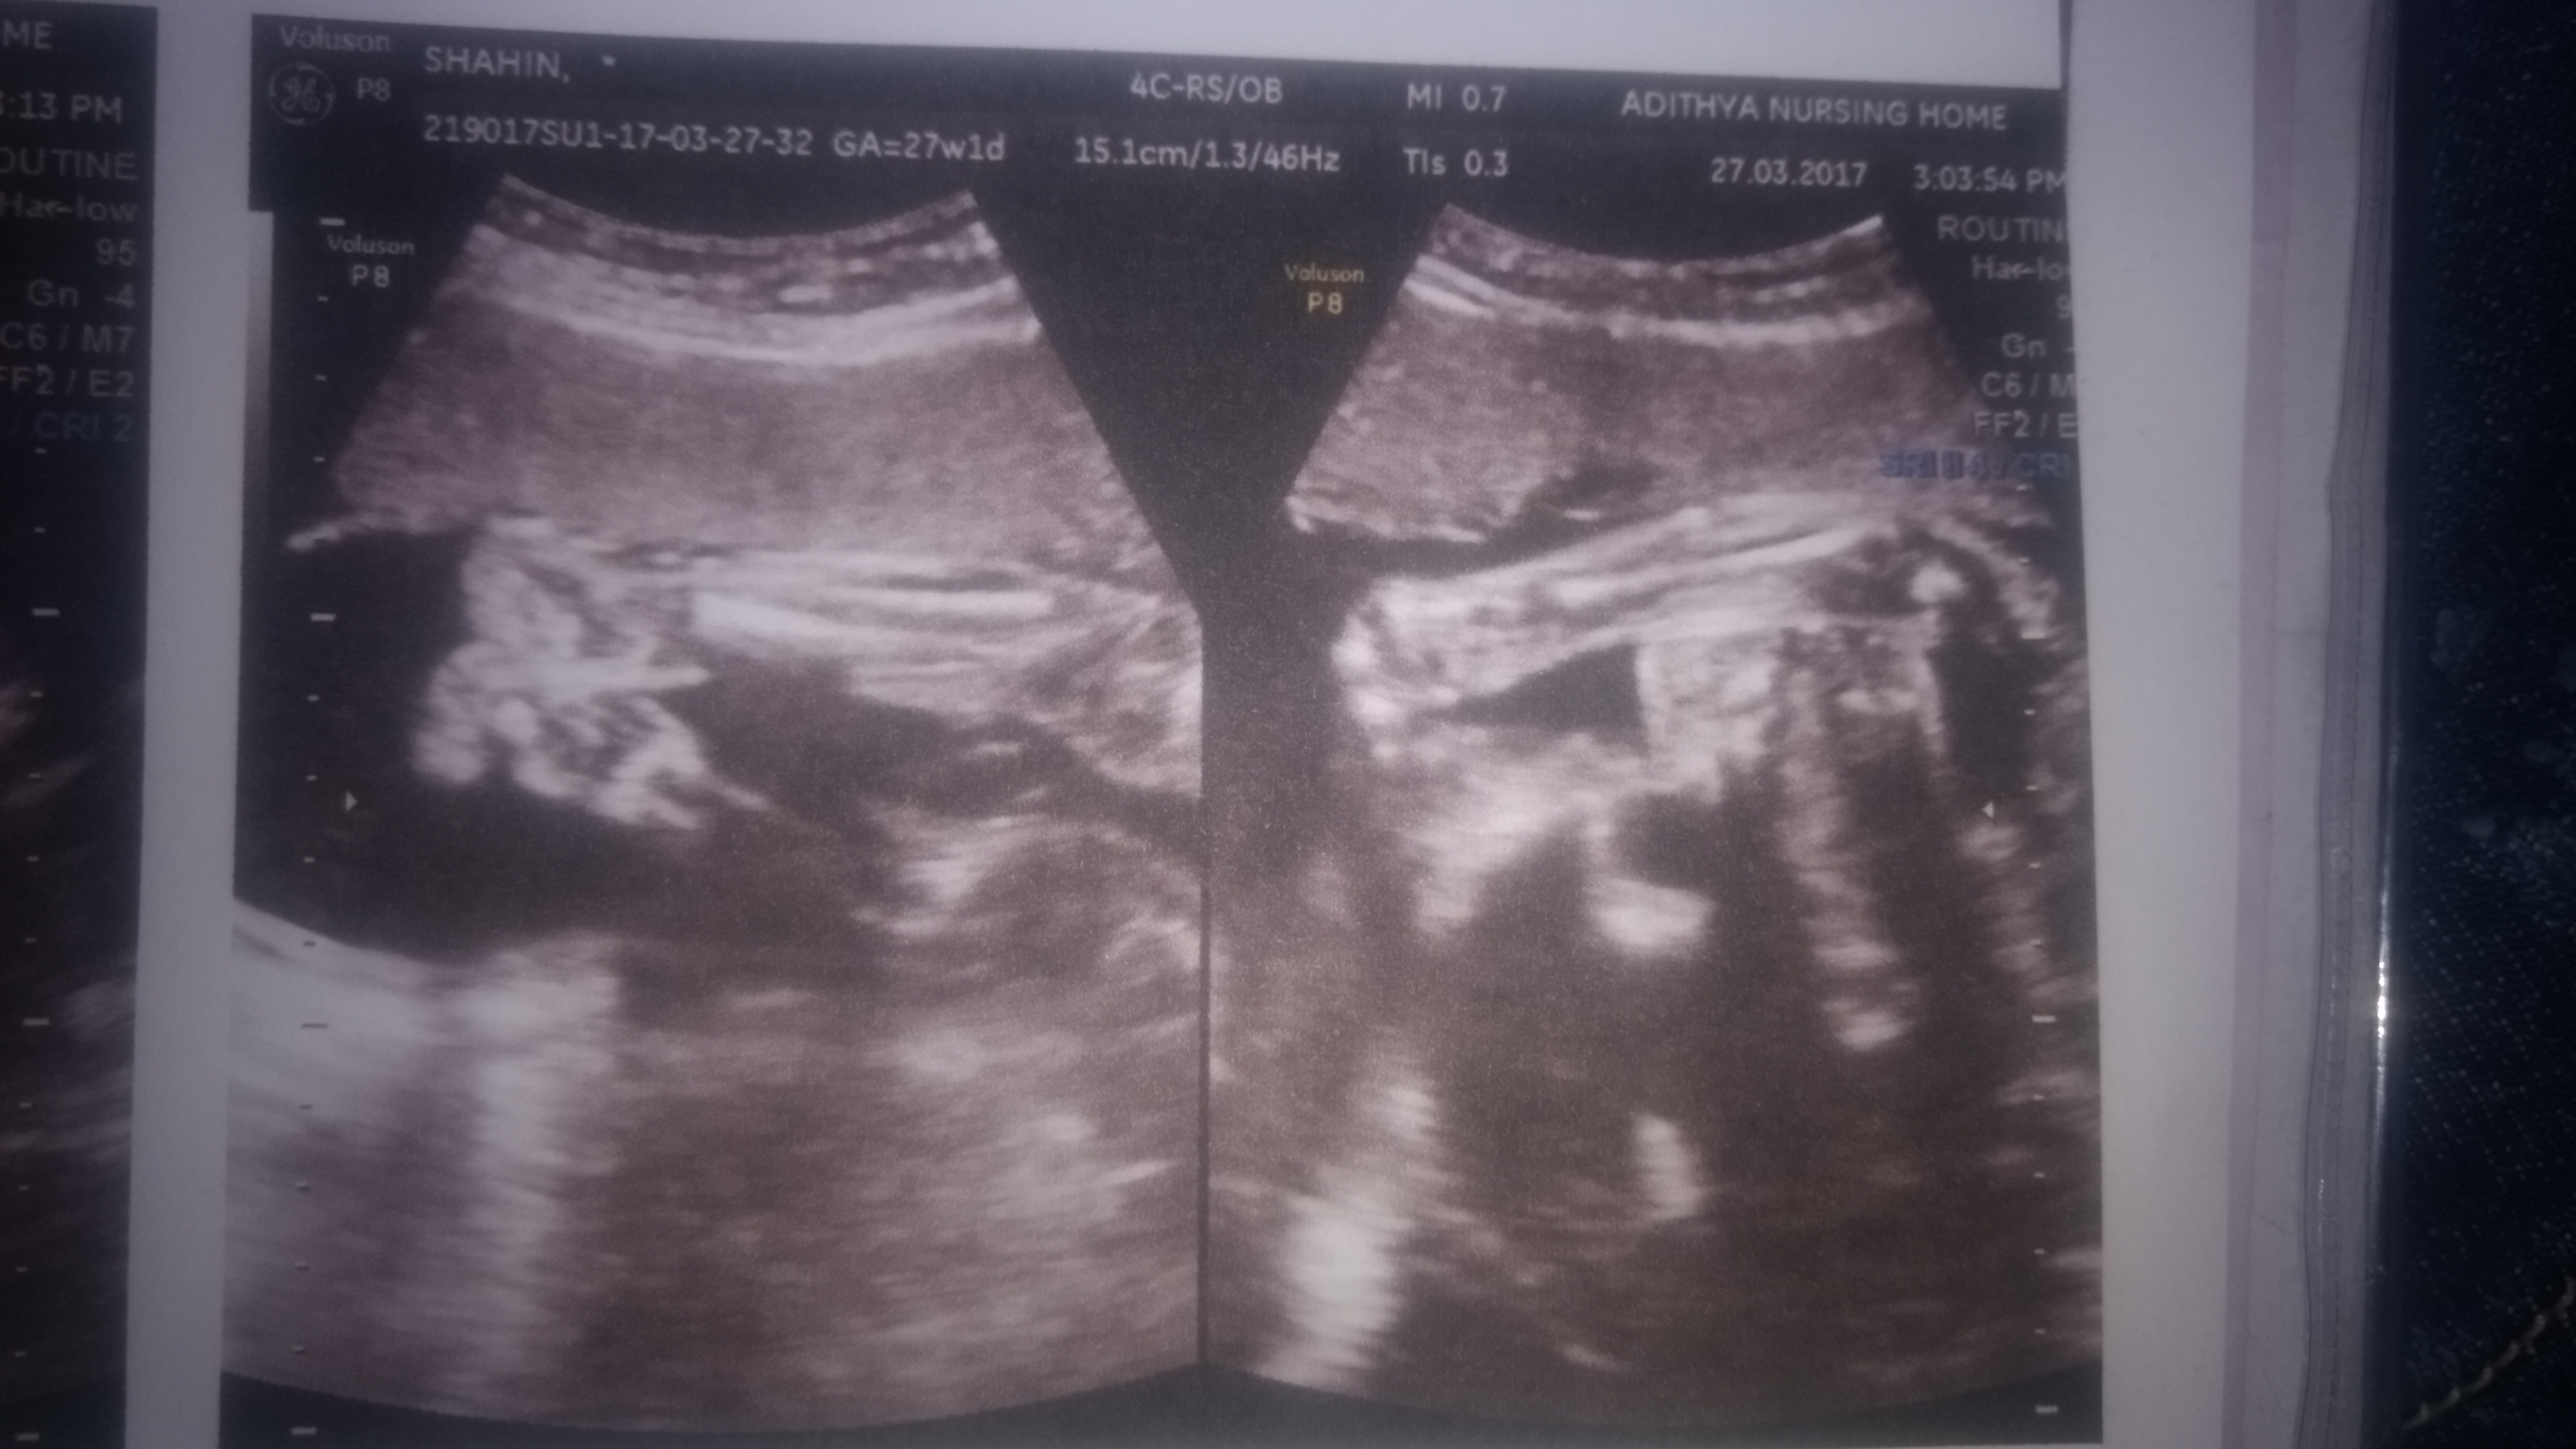

Boy lean [emoji170] Wysłane z iPhone za pomocą Tapatalk

what is that a long one, isn't a willy?